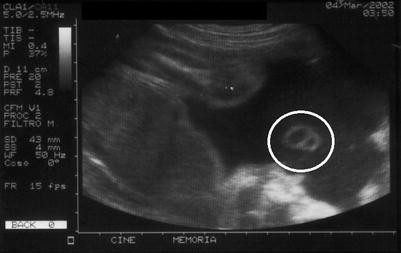

Umbilical Cord Cyst Management : Umbilical cord cysts are classified as true cysts or pseudocysts.